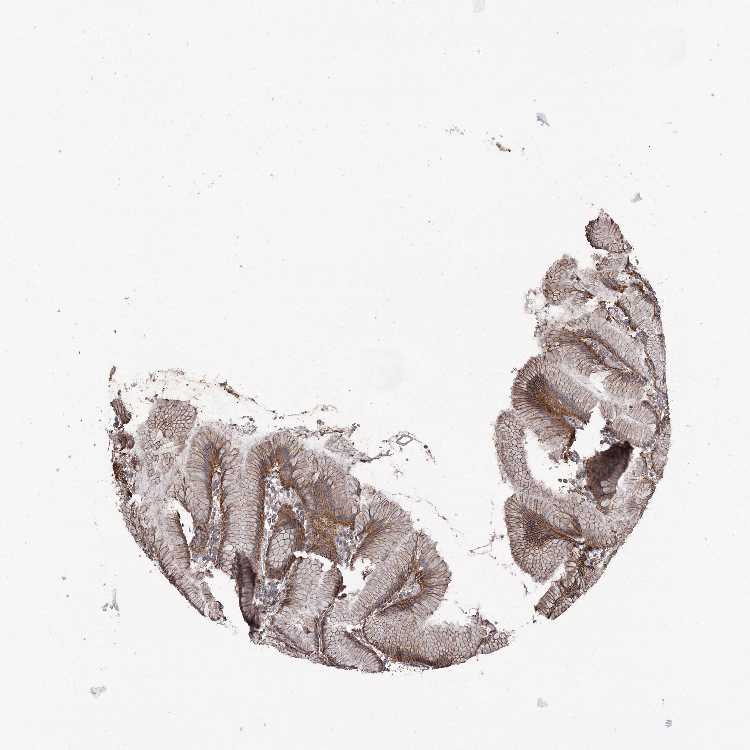

STOMACH 1 - Antibody stainingi

Antibody staining in the annotated cell types in the current human tissue is reported as not detected, low, medium, or high, based on conventional immunohistochemistry profiling in selected tissues. This score is based on the combination of the staining intensity and fraction of stained cells.

Each image is clickable and will lead to virtual microscopy that enables deeper exploration of all samples and also displays staining intensity scores, fraction scores and subcellular localization as well as patient and tissue information for each sample.

Antibody HPA034955Antibody HPA034956

Glandular cells HighHigh